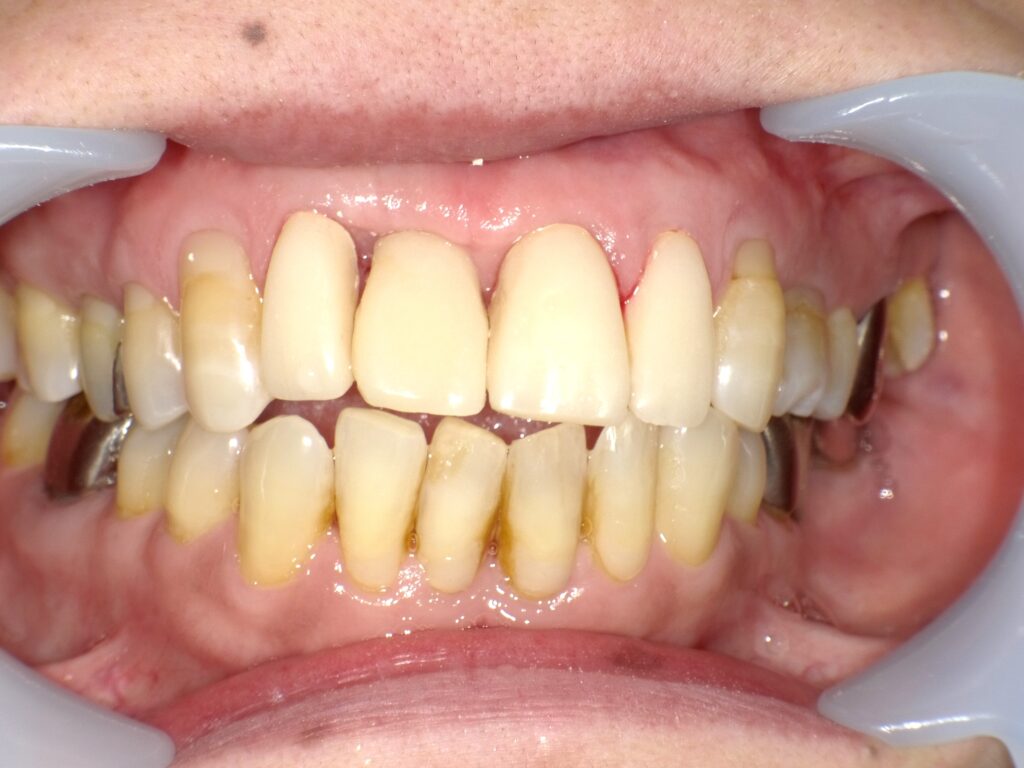

症例一覧 インプラント症例1 2024.11.25 治療内容インプラント主訴前歯部破折したためインプラント治療を行いたい費用¥671,000(1本)治療期間8ヶ月 インプラント症例2 前の記事 インビザライン症例2 次の記事